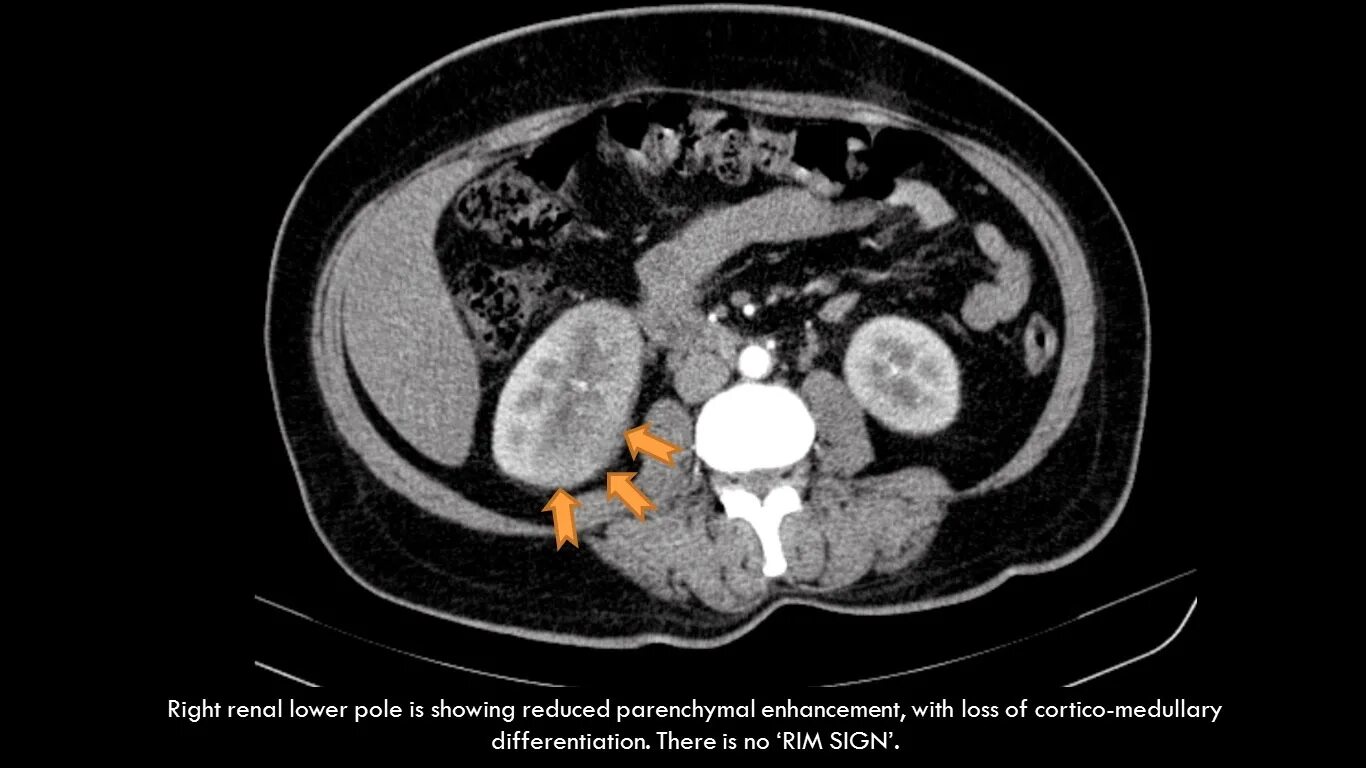

Пиелонефрит кт